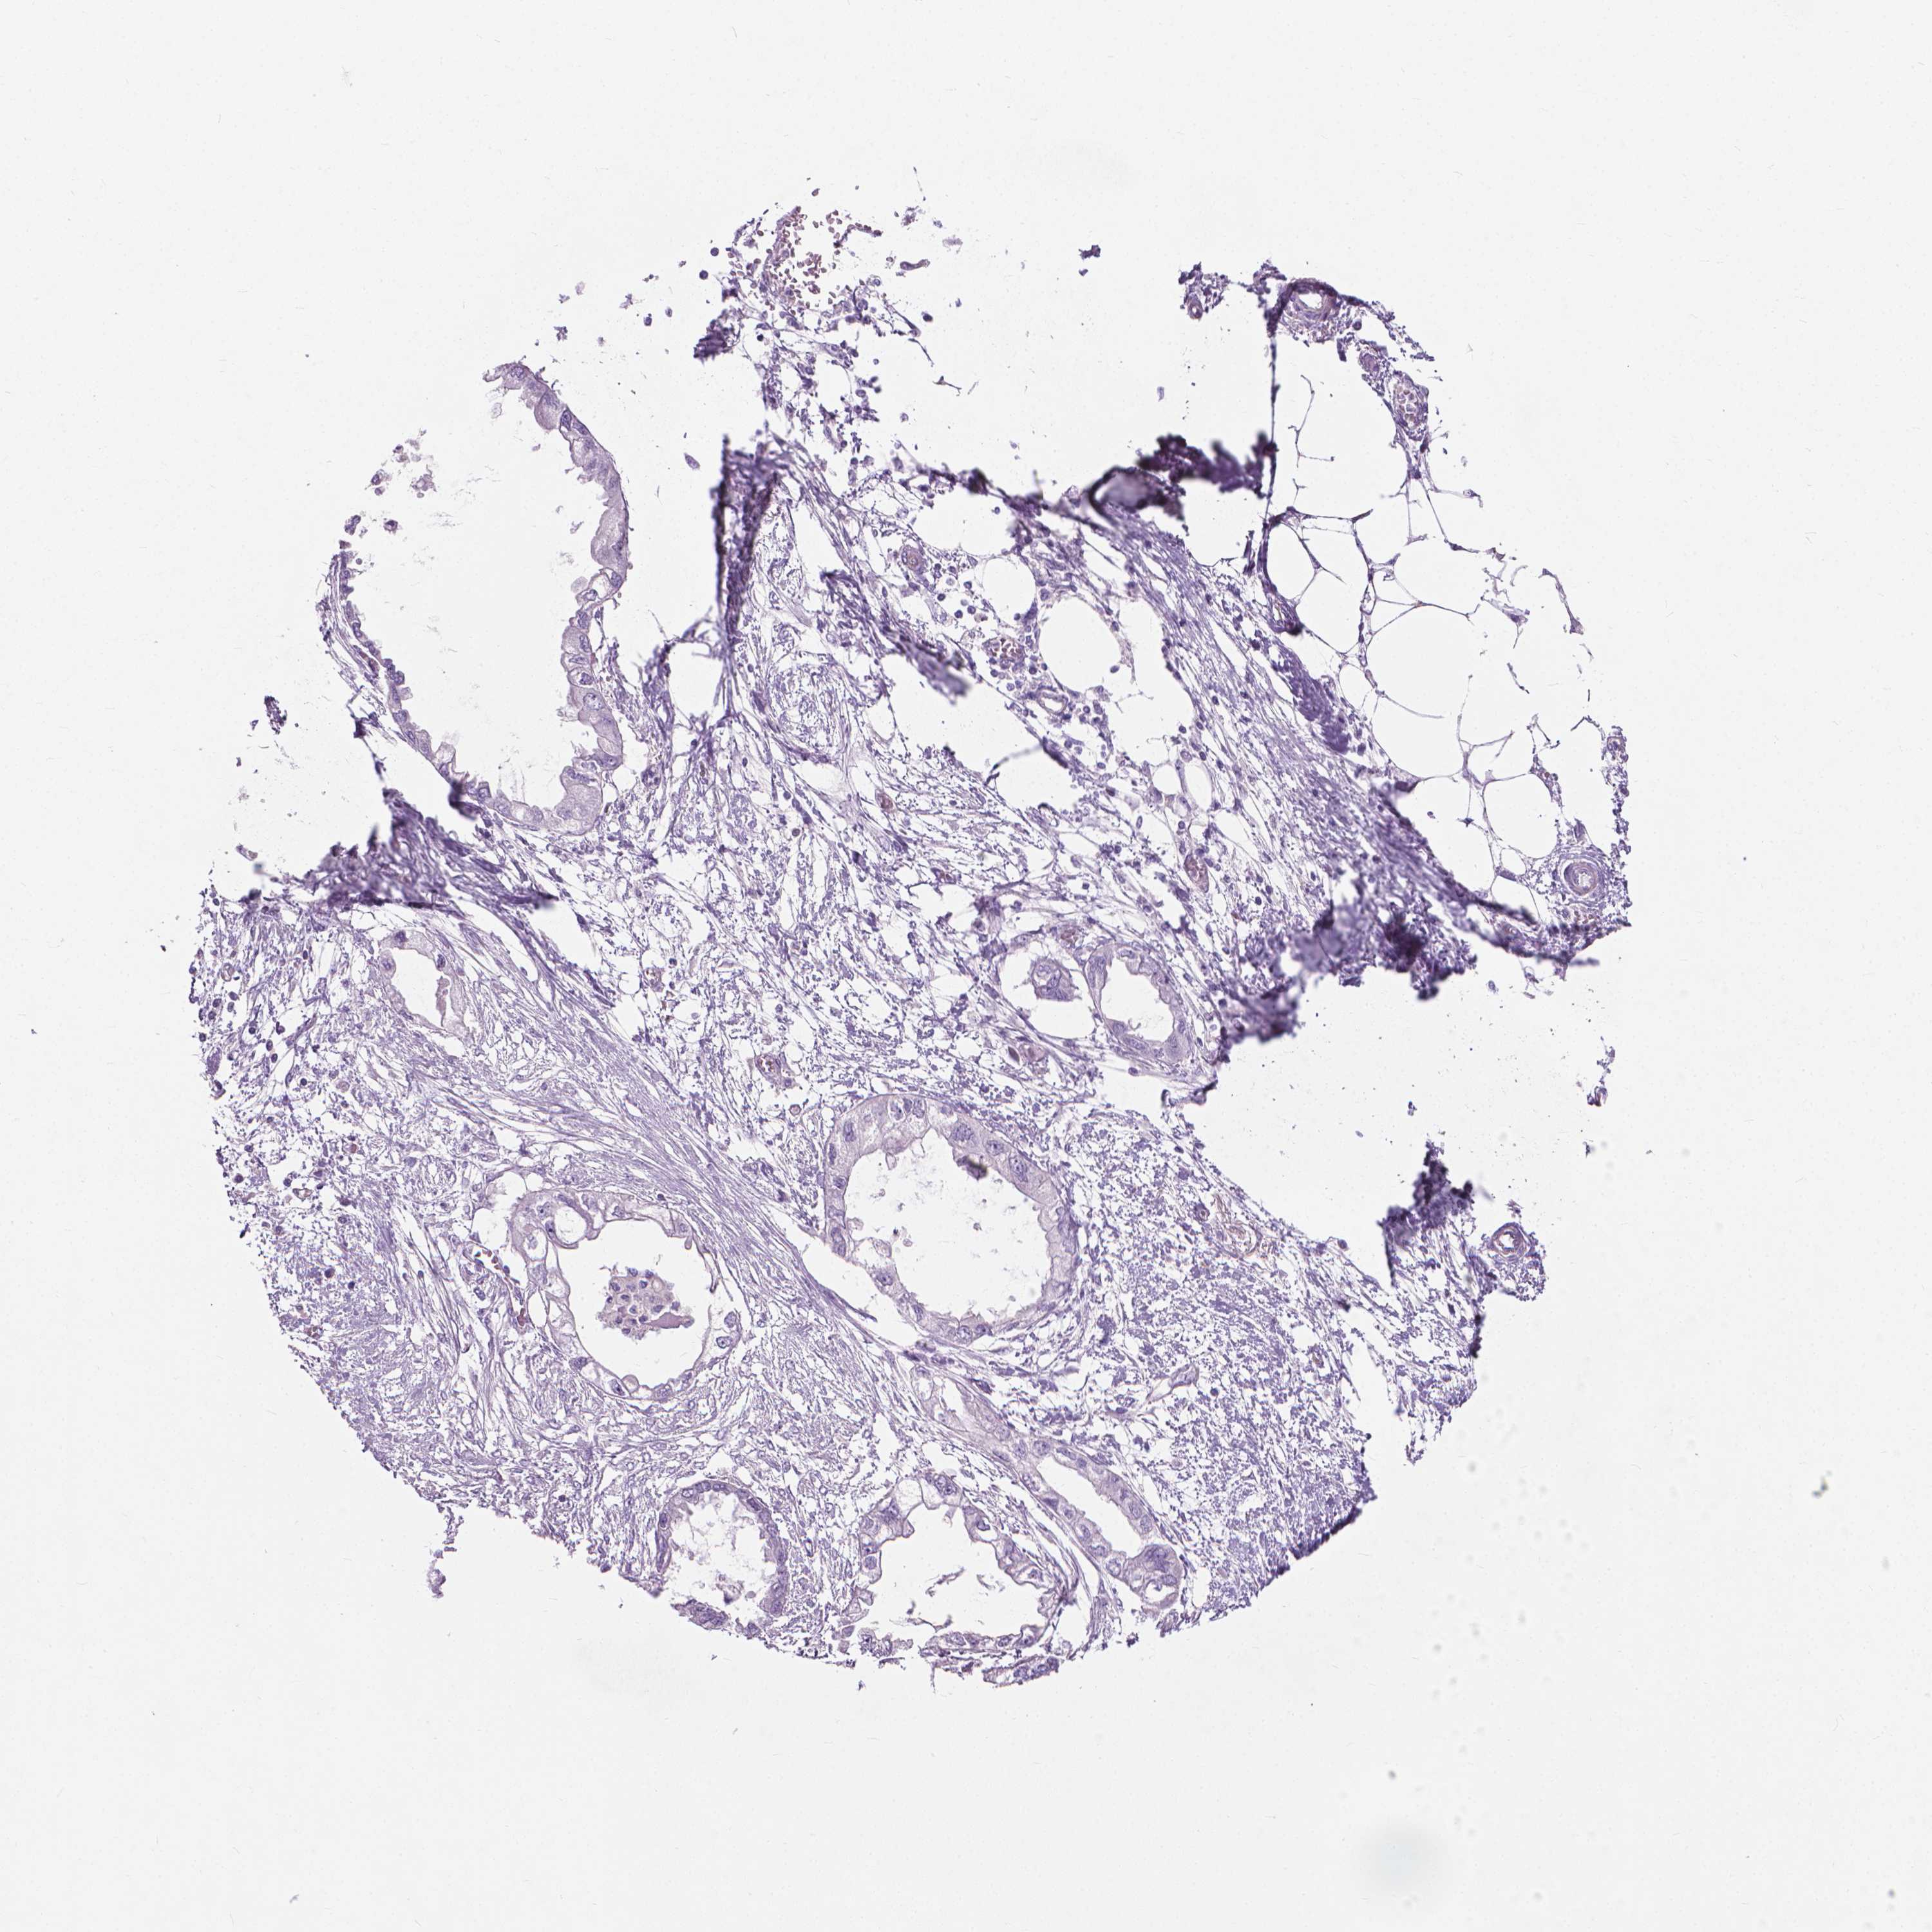

ENDOMETRIAL CANCER - Protein expressioni

A mouse-over function shows sample information and annotation data. Click on an image to view it in a full screen mode. Samples can be filtered based on level of antibody staining by selecting one or several of the following categories: high, medium, low and not detected. The assay and annotation is described here.

Note that samples used for immunohistochemistry by the Human Protein Atlas do not correspond to samples in the TCGA dataset.

Antibody stainingi

Antibody staining in the annotated cell types in the current human tissue is reported as not detected, low, medium, or high, based on conventional immunohistochemistry profiling in selected tissues. This score is based on the combination of the staining intensity and fraction of stained cells.

Each image is clickable and will lead to virtual microscopy that enables deeper exploration of all samples and also displays staining intensity scores, fraction scores and subcellular localization as well as patient and tissue information for each sample.

Antibody HPA044031

Staining

High

Medium

Low

Not detected

Intensity

Strong

Moderate

Weak

Negative

Quantity

>75%

75%-25%

<25%

None

Location

Nuclear

Cytoplasmic/membranous

Cytoplasmic/membranous,nuclear

Adenocarcinoma, NOS

Adenocarcinoma, metastatic, NOS